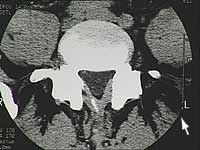

Vous pouvez visualiser sur ce CT l’image d’une hernie discale média latérale.

Hier das Bild einer Computertomographie. Der dreieckige Wirbelkanal, sollte sauber abgegrenzt sein.

Führen Sie Ihren Mauszeiger über das Bild um die mediolaterale Hernie zu sehen. |

Bild 1: kleine linkslaterale Hernie Bild 2: breitbasige Protrusion |

Bild 1: Normale CT. Bei den Hernien-ähnlichen Aufhellungen handelt es sich um die zwei abgehenden Spinalnerven.

Bild 2: Cette hernie par exemple occupe 1/3 du canal rachidien et n’a pourtant pas dû être opérée. |